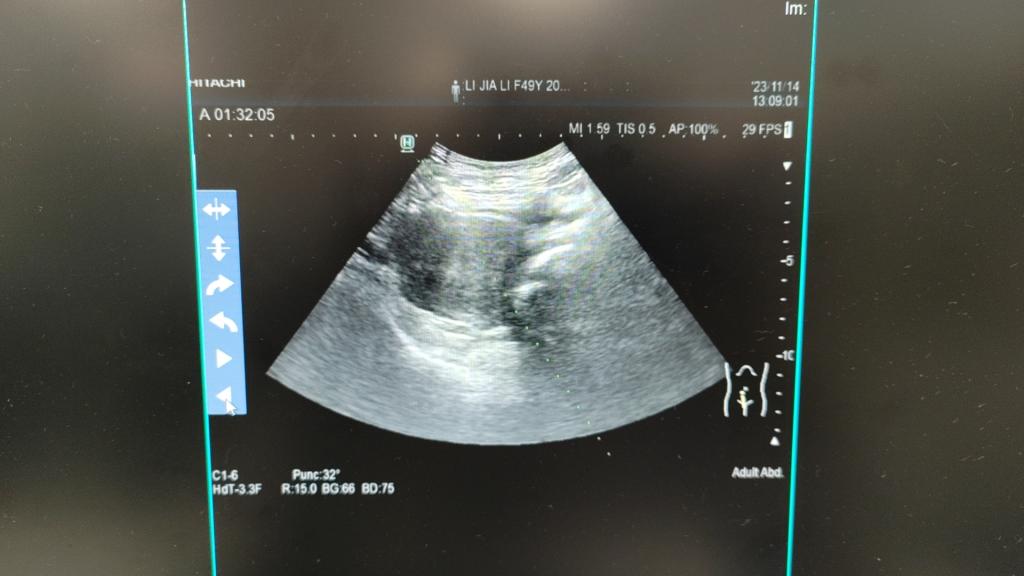

患者李某49岁,因“次全子宫切除术后8年,检查发现盆腔肿物1年,尿频及腹痛腰痛持续无好转”于2023年11月12日入院。患者8年前因子宫腺肌症行次全子宫切除术,1年前患者因尿频、腹胀已在我院检查发现盆腔肿物大小约85*79*62mm,考虑宫颈占位,当时建议行开腹手术切除肿瘤,但其因害怕术后疼痛拒绝开腹手术,直到今年患者持续尿频、腹痛、腰痛才再次到医院复诊,超声及磁共振检查提示肿瘤有所增大约94*75*76mm,考虑宫颈肌瘤可能。建议其首选开腹手术,但其仍然坚决拒绝,其诉求一是不开腹,二是不切除宫颈。我院妇科二病区梁月秀主任与患者及家属耐心沟通后,告知还有另外一个选择,就是微波消融术,患者及家属听闻该手术为微无创手术,手术精准,术后无疼痛,无疤痕,立即决定住院行宫颈病灶微波消融术。

2023年11月14日,我院妇科二病区主任梁月秀带领团队,在麻醉科覃福兴医师、超声科专家利青及麻海智医师的协作下,在全身麻醉下为患者成功施行了超声引导下人工腹水+超声引导下宫颈病灶微波消融术+宫颈病灶穿刺活检术+宫颈病灶穿刺注射聚桂醇硬化治疗。术中,我院妇科二病区梁月秀主任团队运用娴熟的操作技术,在超声引导下合理选择手术入路,将微波消融针直接穿刺到病变部位,对患者病灶进行了多点位消融灭活,由消融针释放的热磁场可以使周围的分子高速旋转运动并摩擦升温,从而使消融区组织发生不可逆凝固性坏死,使病灶缩小或逐渐消失,达到治疗的目的。消融后,梁月秀主任团队再次用超声造影即刻评估消融灶无血供区达到预期,准确迅速地完成了此例次全子宫切除术后宫颈病灶微波消融术。